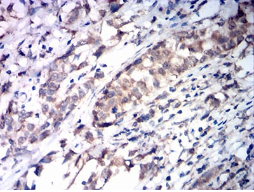

SDHB Mouse Monoclonal antibody[2E8B1]

Species Reactivity:    Human

IHC    1/200 - 1/1000